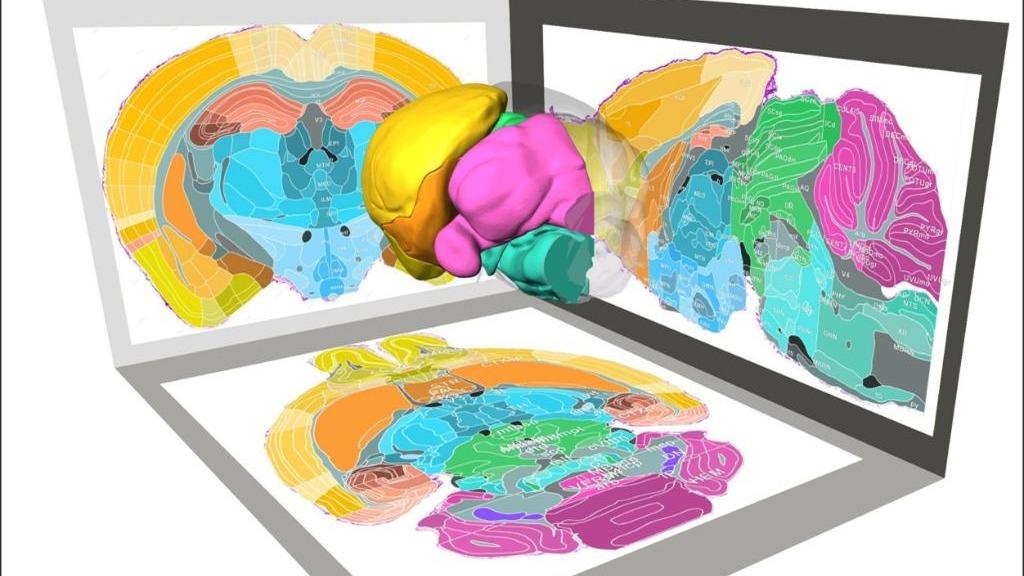

150多间石屋藏于峭壁 山西盂县发现一处明代古寨遗址

记者日前从海南大学获悉,该校校长骆清铭院士团队联合华中科技大学,研发出全脑细胞架构解析平台,能够获取小鼠全脑的连续图像,绘制出20种关键类型细胞的全脑三维分布图,揭示脑区存在精细组织模式及大脑皮层与小2025-12-03 -